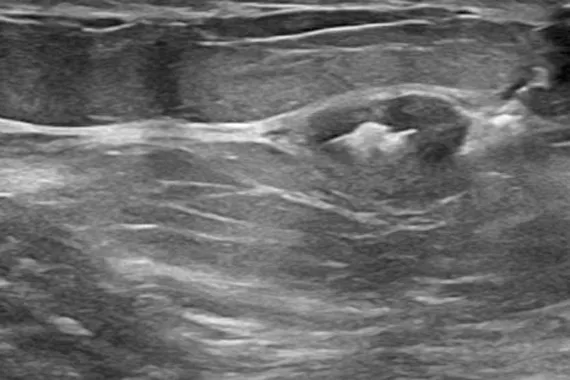

The Hologic range of biopsy site markers come in multiple shapes, gauges and lengths. The markers are compatible for use with x-ray, ultrasound and MRI guided biopsies. All markers come with an ergonomic and easy to use deployment device included.

Designed to minimise movement,2 this marker is highly visible in ultrasound upon deployment and still highly visible at 6 weeks post-biopsy, crucial in case of future breast interventions.3 The marker consists of two pieces, a permanent marker and a bioabsorbable suture-like netting.

say ultrasound visibility was good to excellent upon deployment1